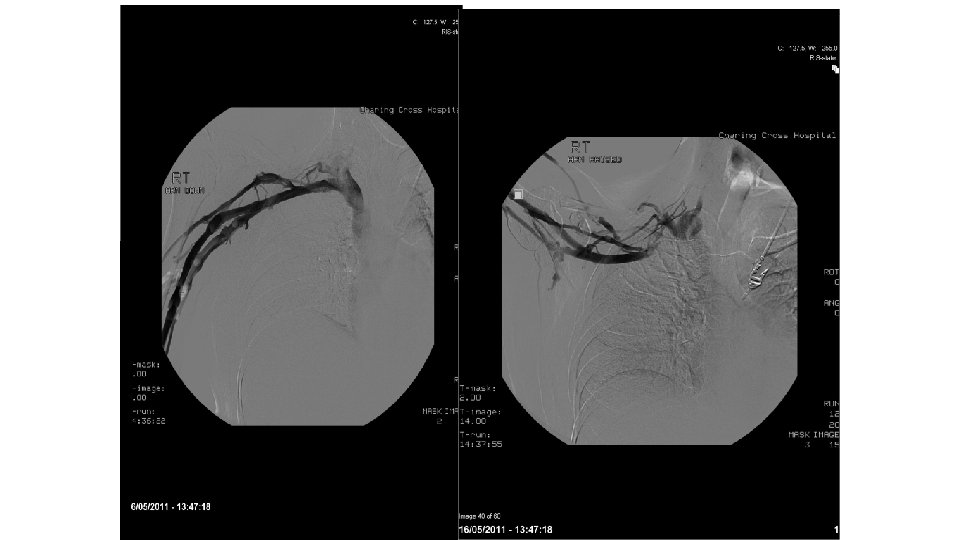

Paget-Schroetter syndrome therapy: failure of intravenous stents. • 22 patients had intravenous stents placed post-thrombolysis for Paget-Schroetter syndrome. All had post stent anticoagulation. In all patients the subclavian vein reoccluded 1 day to 6 weeks after stent insertion. Urschel HC et al, Ann Thorac Surg. 2003

• Primary subclavian vein stents are not recommended for venous thoracic outlet syndrome before surgical decompression by first rib resection due to a high risk of fracture because they are compressed between the clavicle and first rib.